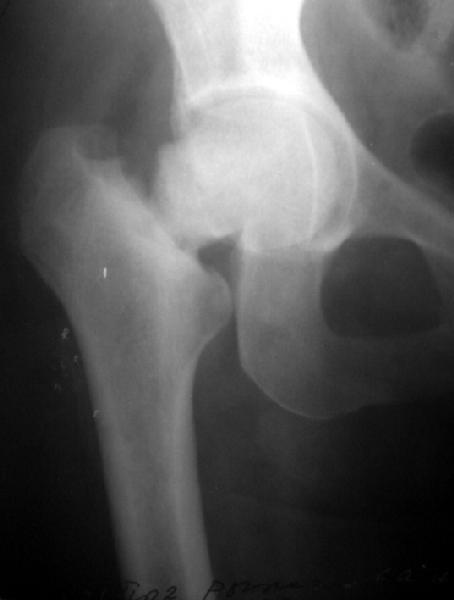

Женщина лет 40 переведена к нам из городской больницы с переломом шейки бедра.

Упала дома 5.11.02. С ее слов, в послдений год лечилась консервативно от якобы коксартроза с этой же стороны. Снимков не делали. Этот сустав болит последние несколько месяцев. На снимках обращает на себя "замыленность" краев. Не усталостный ли это перелом? Дама полноватая. Ограничения амплитуды движений до травмы она не отмечала. Мнения о тактике у нас разошлись в диапазоне от остеосинтеза винтами до эндопротезирования, с остеотомиями между ними. Помогите, пожалуйста, обосновать выбор.